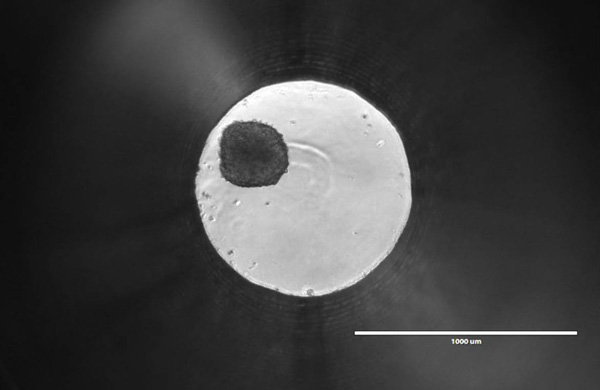

There’s something beautiful about the tiny ball I’m looking at through the microscope. It’s only about 200—250 microns in diameter, smaller than a single grain of salt. As I bump the plate with my finger, the ball rolls around the 1mm well. To me, it may just look like a dark spot within an illuminated circle, but many scientists feel it could represent the future of oncology research and drug discovery.

It’s a Friday afternoon, and I’m staring at a spheroid of roughly 1,000 human liver cells. Promega Research Scientist Mike Valley heard that I was interested in 3-dimensional cell culture models, so he invited me over to his lab in the Research and Development Center to check out the spheroids for myself. Mike is developing a new assay, and with recent trends in cell biology research, he knows it’s crucial to optimize that assay for use with 3D cultures.

In 2D culture, cells are typically plated in a flat monolayer. One-sided attachment induces a polarity that is unnatural for many cells. It also means that each cell is getting equal access to nutrients and oxygen, resulting in uniform growth and proliferation. Each cell is likely at the same metabolic state, which is rare in the body. Tumors, in contrast, show high levels of heterogeneity, with some cells actively proliferating, others quiescent, and some necrotic. This issue is less prevalent in 3D spheroids, where nutrient gradients emerge gradually as the diameter increases. As the spheroid grows, the cells in the core begin to experience reduced oxygen exposure. This results in a hypoxia gradient, which can lead inner layers to quiescence and even necrosis.